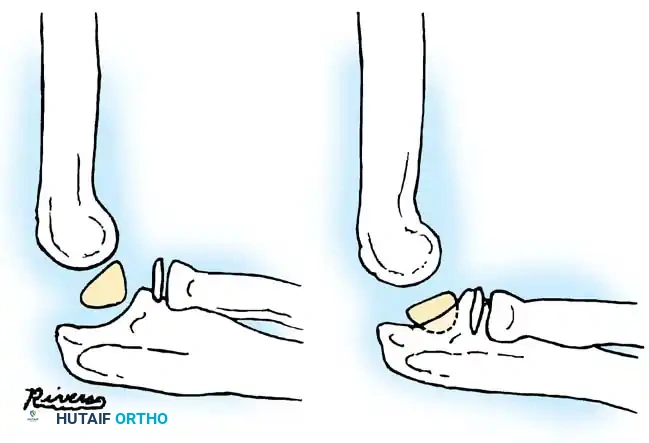

In cases of chronic radial head dislocation (often missed acutely or associated with plastic deformation of the ulna), simple open reduction is insufficient. The Hirayama Technique utilizes an ulnar osteotomy to overcorrect the angular deformity, thereby pulling the radial head back into the joint via the interosseous membrane.

TECHNIQUE 33-5: Osteotomy of the Ulna (Hirayama et al.)

- Preparation: Inflate a pneumatic tourniquet. Make a posterolateral skin incision exposing the radiohumeral joint and proximal third of the ulna. Excise intra-articular scar tissue.

- Osteotomy: Perform a subperiosteal osteotomy of the ulna 5 cm distal to the olecranon.

- Distraction and Angulation: Distract the osteotomy by 1 cm to lengthen the ulna.

- For Anterior Dislocation: Correct by posterior angulation of the ulna.

- For Lateral Dislocation: Correct by medial angulation of the ulna.

- Fixation: Secure the osteotomy with a metal plate bent to approximately 15 degrees. Ensure the radial head rests perfectly within the radial notch of the ulna without excessive radiocapitellar pressure.

- Closure: Approximate the anconeus. Do not repair the annular ligament, as this can restrict rotation.

- Postoperative Care: Apply a plaster splint in 90 degrees of flexion and full supination for 4 weeks, followed by aggressive active range of motion.

Fig. 33-36 Overcorrection with posterior convexity for anterior dislocation.

Fig. 33-37 Overcorrection with medial convexity for lateral dislocation.